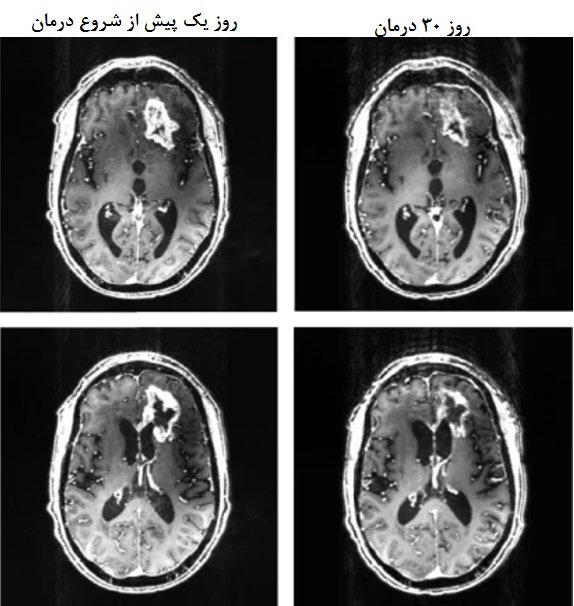

محققان به عنوان بخشی از آخرین دستاورد حوزه علوم اعصاب، با استفاده از کلاه ایمنی دارای میدان مغناطیسی توانستهاند یک تومور مغزی کشنده را کوچک کنند. این تحقیقات بر روی بیماری ۵۳ ساله انجام شده است که در نهایت بر اثر جراحات دیگری از دنیا رفت. اما در نمونه برداری از مغز این فرد پس از کالبدشکافی مشخص شد که این فرآیند بهصورت موفقیتآمیزی توانسته ۳۱ درصد از حجم این تومور را در مدت کوتاهی کاهش دهد. این آزمون به عنوان اولین روش درمانی غیرتهاجمی درمان نوع کشندهای از تومورهای مغزی به نام گلیوبلاستوما معرفی شده است.

در این کلاه ایمنی از سه آهنربای چرخان استفاده شده است که به کنترلکننده الکترونیکی مبتنی بر ریزپردازنده که با استفاده از باتری قابل شارژ کار میکند، متصل است. در بخشی از این روش درمانی، بیمار به مدت پنج هفته در مرکز درمانی و سپس در خانه با کمک همسرش از این تجهیز استفاده میکرده است. درمان با میدان مغناطیسی ایجاد شده درون کلاه در ابتدا به مدت دو ساعت در روز بر روی بیمار انجام میشد و به تدریج تا شش ساعت در روز افزایش یافته است. در طول دوره درمانی، جرم و حجم تومور بیمار نزدیک به یک سوم کاهش یافت به طوری که به نظر میرسید میان دوز درمانی و میزان کاهش ابعاد تومور رابطهای برقرار است.